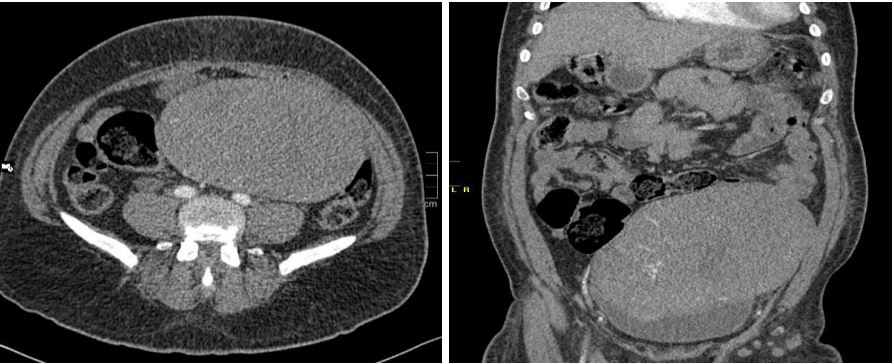

In December 2021, a 54-year-old diabetic man presented a pelvic discomfort. Clinical examination revealed a painless abdominopelvic mass measuring approximately 20 cm in length and 10 cm in height. The mass was mobile relatively to both superficial and deep tissue planes. An abdominopelvic CT scan revealed a heterogeneous abdominopelvic mass with regular contours, located centrally, and showing heterogeneous enhancement upon contrast medium administration.

The tumor was multinodular, arising from the prostate and causing displacement of large blood vessels. The tumor measures 23 × 21 × 15 cm (Figure 1). The mass displayed a homogeneous beige-white appearance, with a lobulated structure and no evidence of necrosis (Figure 2).

Figure 1: Imaging of prostatic SFT. Pelvic axial CT-scan detecting a medial massive mass lesion in pelvic regions.